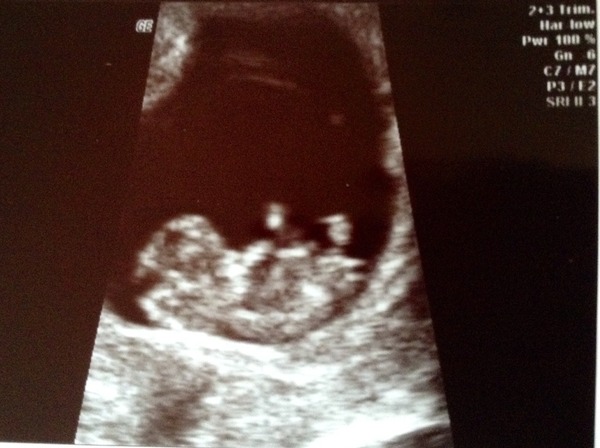

Here's my little stumpy legged bean! I was surprised just how baby like it looked, even though it's still quite blobby. I can't stop looking at the photo and still can't quite make the connection that what is in the picture is squirming around inside of me!

sara that scan picture is amazing! Congrats!

Love the scan piccy sara it does look like a proper baby!! I had mine at 6+4 and now I'm wishing id waited until now as I just want to see him/her again and still got 2 weeks 5 days (yes I'm counting) until my 12 week scan.